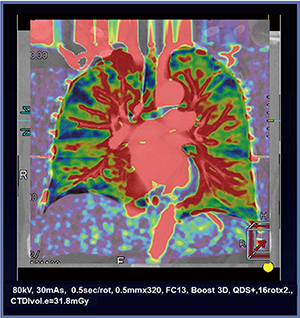

また,2008年のDynamic CT, Dynamic MRIおよびPETなどのMeta Analysisによる検討で,これらの手法における良・悪性結節鑑別診断法には有意差がないことが示唆されたが9),われわれの検討ではDynamic CE-perfusion ADCTを用いることにより,Dynamic MRI with ultra-short TEおよびPET/CTに比して,より診断能高く肺結節を診断することが可能であるということも知られている6)。さらに,このDynamic CE-perfusion ADCTをAIDR 3Dと併用することにより被ばく低減を行いながら複数ボリュームで行うことと,東芝メディカルシステムズ社と共同開発中のソフトウエアの臨床応用により,全肺Dynamic CE-perfusion ADCTをさまざまな疾患で臨床応用可能になるので,今後の呼吸器学,循環器学や放射線医学などのさまざまな発展に貢献することが期待されている(図2)。

図2 全肺Dynamic CE-perfusion ADCT

現在,東芝メディカルシステムズ社と共同開発中のソフトウエアを使用することにより,全肺Perfusion CTがAquilion ONEで可能となる。